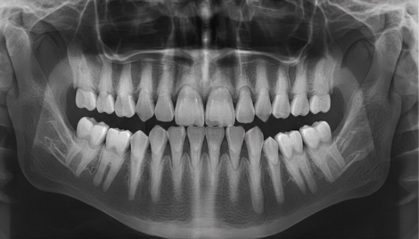

Главная проблема классических слепков заключается в их подверженности деформации. Гипс или силикон могут давать усадку, а малейшее движение пациента во время застывания массы приводит к погрешностям. В вопросах имплантации зубов в Сургуте, где точность измеряется долями миллиметра, такие ошибки недопустимы. Компьютерная томография, выполняемая в медицинском центре «Томакс», предоставляет врачу исчерпывающую информацию не только о коронковой части зуба, но и о состоянии костной ткани, расположении нервных каналов и придаточных пазух носа. Это позволяет создать виртуальный двойник челюсти пациента, на котором можно заранее «прорепетировать» установку имплантата, выбрав оптимальный угол и глубину погружения.

Успех имплантации напрямую зависит от объема и качества костной ткани. Обычный слепок не дает представления о том, что скрыто под десной. КТ челюстно-лицевой области позволяет хирургу-имплантологу оценить плотность кости и близость гайморовых пазух. Если планируется имплантация на верхней челюсти, данные томографии помогут определить необходимость проведения синус-лифтинга. Благодаря 3D-снимку врач может изготовить навигационный шаблон — специальное устройство, которое направляет сверло и имплантат точно в запланированное место. Это делает операцию менее травматичной, сокращает время реабилитации и практически сводит к нулю риск отторжения из-за неправильной установки.

В ортопедической стоматологии КТ челюсти помогает добиться идеальной эстетики и функциональности. При создании виниров или мостовидных протезов важно учитывать особенности прикуса и височно-нижнечелюстного сустава. Трехмерное сканирование дает возможность оценить работу суставов в динамике, что предотвращает появление сколов керамики или дискомфорта при жевании в будущем. Пациенты в Сургуте все чаще выбирают безметалловую керамику и циркониевые коронки, изготовление которых требует цифровой точности. Интеграция данных КТ в зуботехническую лабораторию позволяет создавать протезы, которые ощущаются как собственные зубы с первого дня установки.